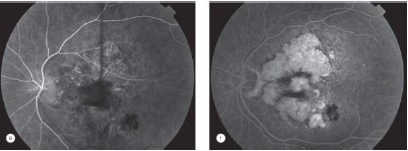

Describe the follow pictures

RPE detachment

Course?

1. RPE TEAR

RPE tear

Describe image?

Detachment= dome ( fluid pushed up)

Tear= flap

Patient c/o vision loss